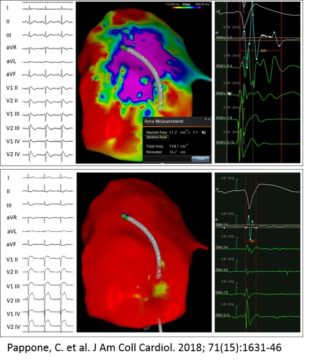

Through the use of dedicated software that is associated with mapping systems, it is possible to reconstruct the three-dimensional geometry of the heart and to identify with precision the areas of myocardium affected by the disease (figure 2).

To achieve this goal, it is necessary to administer ajmaline during this mapping phase. This drug is able to unmask the cardiac electrical anomalies to the maximal degree, enabling the visualization and pronounced definition of the area of anomalous substrate to be treated.

Once the anomalous electrical substrate has been identified, it is possible to perform the ablation of this area. Radiofrequency disbursements are rapid and precise, in order to limit ablation to only the outer surface of the heart, enabling the elimination of only surface cells (figure 3).

The purpose of the ablation is to eliminate all the anomalous electric potentials located on the epicardium (figure 4), resulting in a complete normalization of the electrocardiogram which no longer shows, after ablation, the classical electrical anomalies of BrS (figure 5). These elements are also associated with the disappearance of malignant ventricular arrhythmias in post-ablation follow-up.

- Pappone C, Ciconte G, Manguso F, Vicedomini G, Mecarocci V, Conti M, Giannelli L, Pozzi P, Borrelli V, Menicanti L, Calovic Z, Della Ratta G, Brugada J, Santinelli V. Assessing the Malignant Ventricular Arrhythmic Substrate in Patients With Brugada Syndrome. J Am Coll Cardiol. 2018 Apr 17;71(15):1631-1646. doi: 10.1016/j.jacc.2018.02.022. PubMed PMID: 29650119.